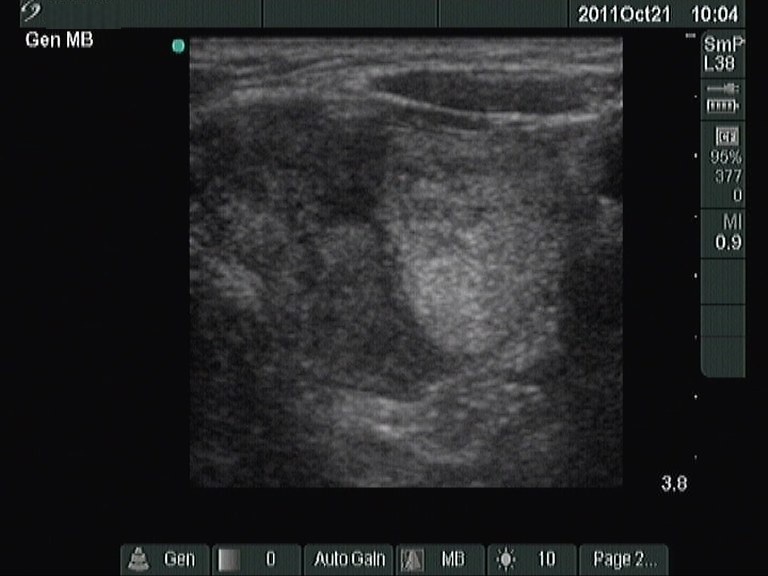

Follow-up examination 2 years later (2nd and 3rd rows of images):

Clinical presentation: the complaints of the patient worsened and requested a repeat examination.

Palpation: there was a nodule in the left lobe.

Hormonal investigation: indicated euthyroidism on daily 87.5 microgram levothyroxine (TSH-level 1.88 mIU/L).

Ultrasonography: was unchanged except for the increase of the left lobe by 38% in volume.Cytology: benign lesion.

It is worth comparing the numerous small echonormal lesions and the large nodule in the left thyroid. The former are part of the so-called pseudonodular form of Hashimoto's thyroiditis, while the true nodule was much larger. Pseudonodules are usually in the range of 5 to 15 mm in maximal diameter.